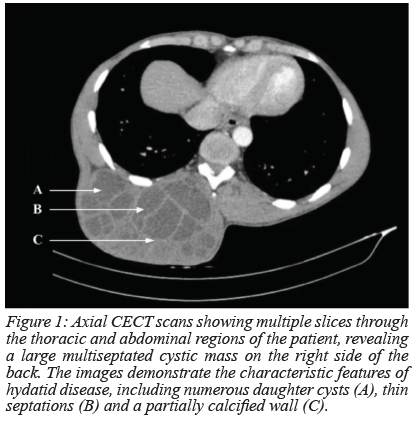

The CECT revealed a large multiseptated cystic mass involving the posterolateral thoracoabdominal paraspinal muscles on the right side of the body. The mass showed characteristic features of hydatid disease, including thin septations, a "honeycomb" pattern with daughter cysts, and a partially calcified wall (Figures 1 and 2). The adjacent structures, including the spine and surrounding soft tissues, appeared to be displaced but not invaded by the mass. There was no pulmonary or hepatic involvement. These findings were consistent with a diagnosis of hydatid disease Type CE2 according to the World Health Organization Classification.1 Given the clinical presentation and radiological findings, hydatid serology was performed, yielding a positive result. Subsequent biochemical analyses revealed no additional abnormalities.

The diagnosis of hydatid disease is based on clinical suspicion, imaging findings, and serological tests. Imaging modalities such as CECT and magnetic resonance imaging (MRI) can help in characterising the cystic mass and assessing its relationship with adjacent structures. Imaging studies may reveal characteristic features of hydatid cysts, including multivesicular lesions and the presence of daughter cysts.9 Serological tests, including hydatid serology, can aid in confirming the diagnosis.9,10 In our case, the positive hydatid serology and characteristic imaging findings on a thoracic and abdominal CECT supported the diagnosis of hydatid disease involving the soft tissue of the back.